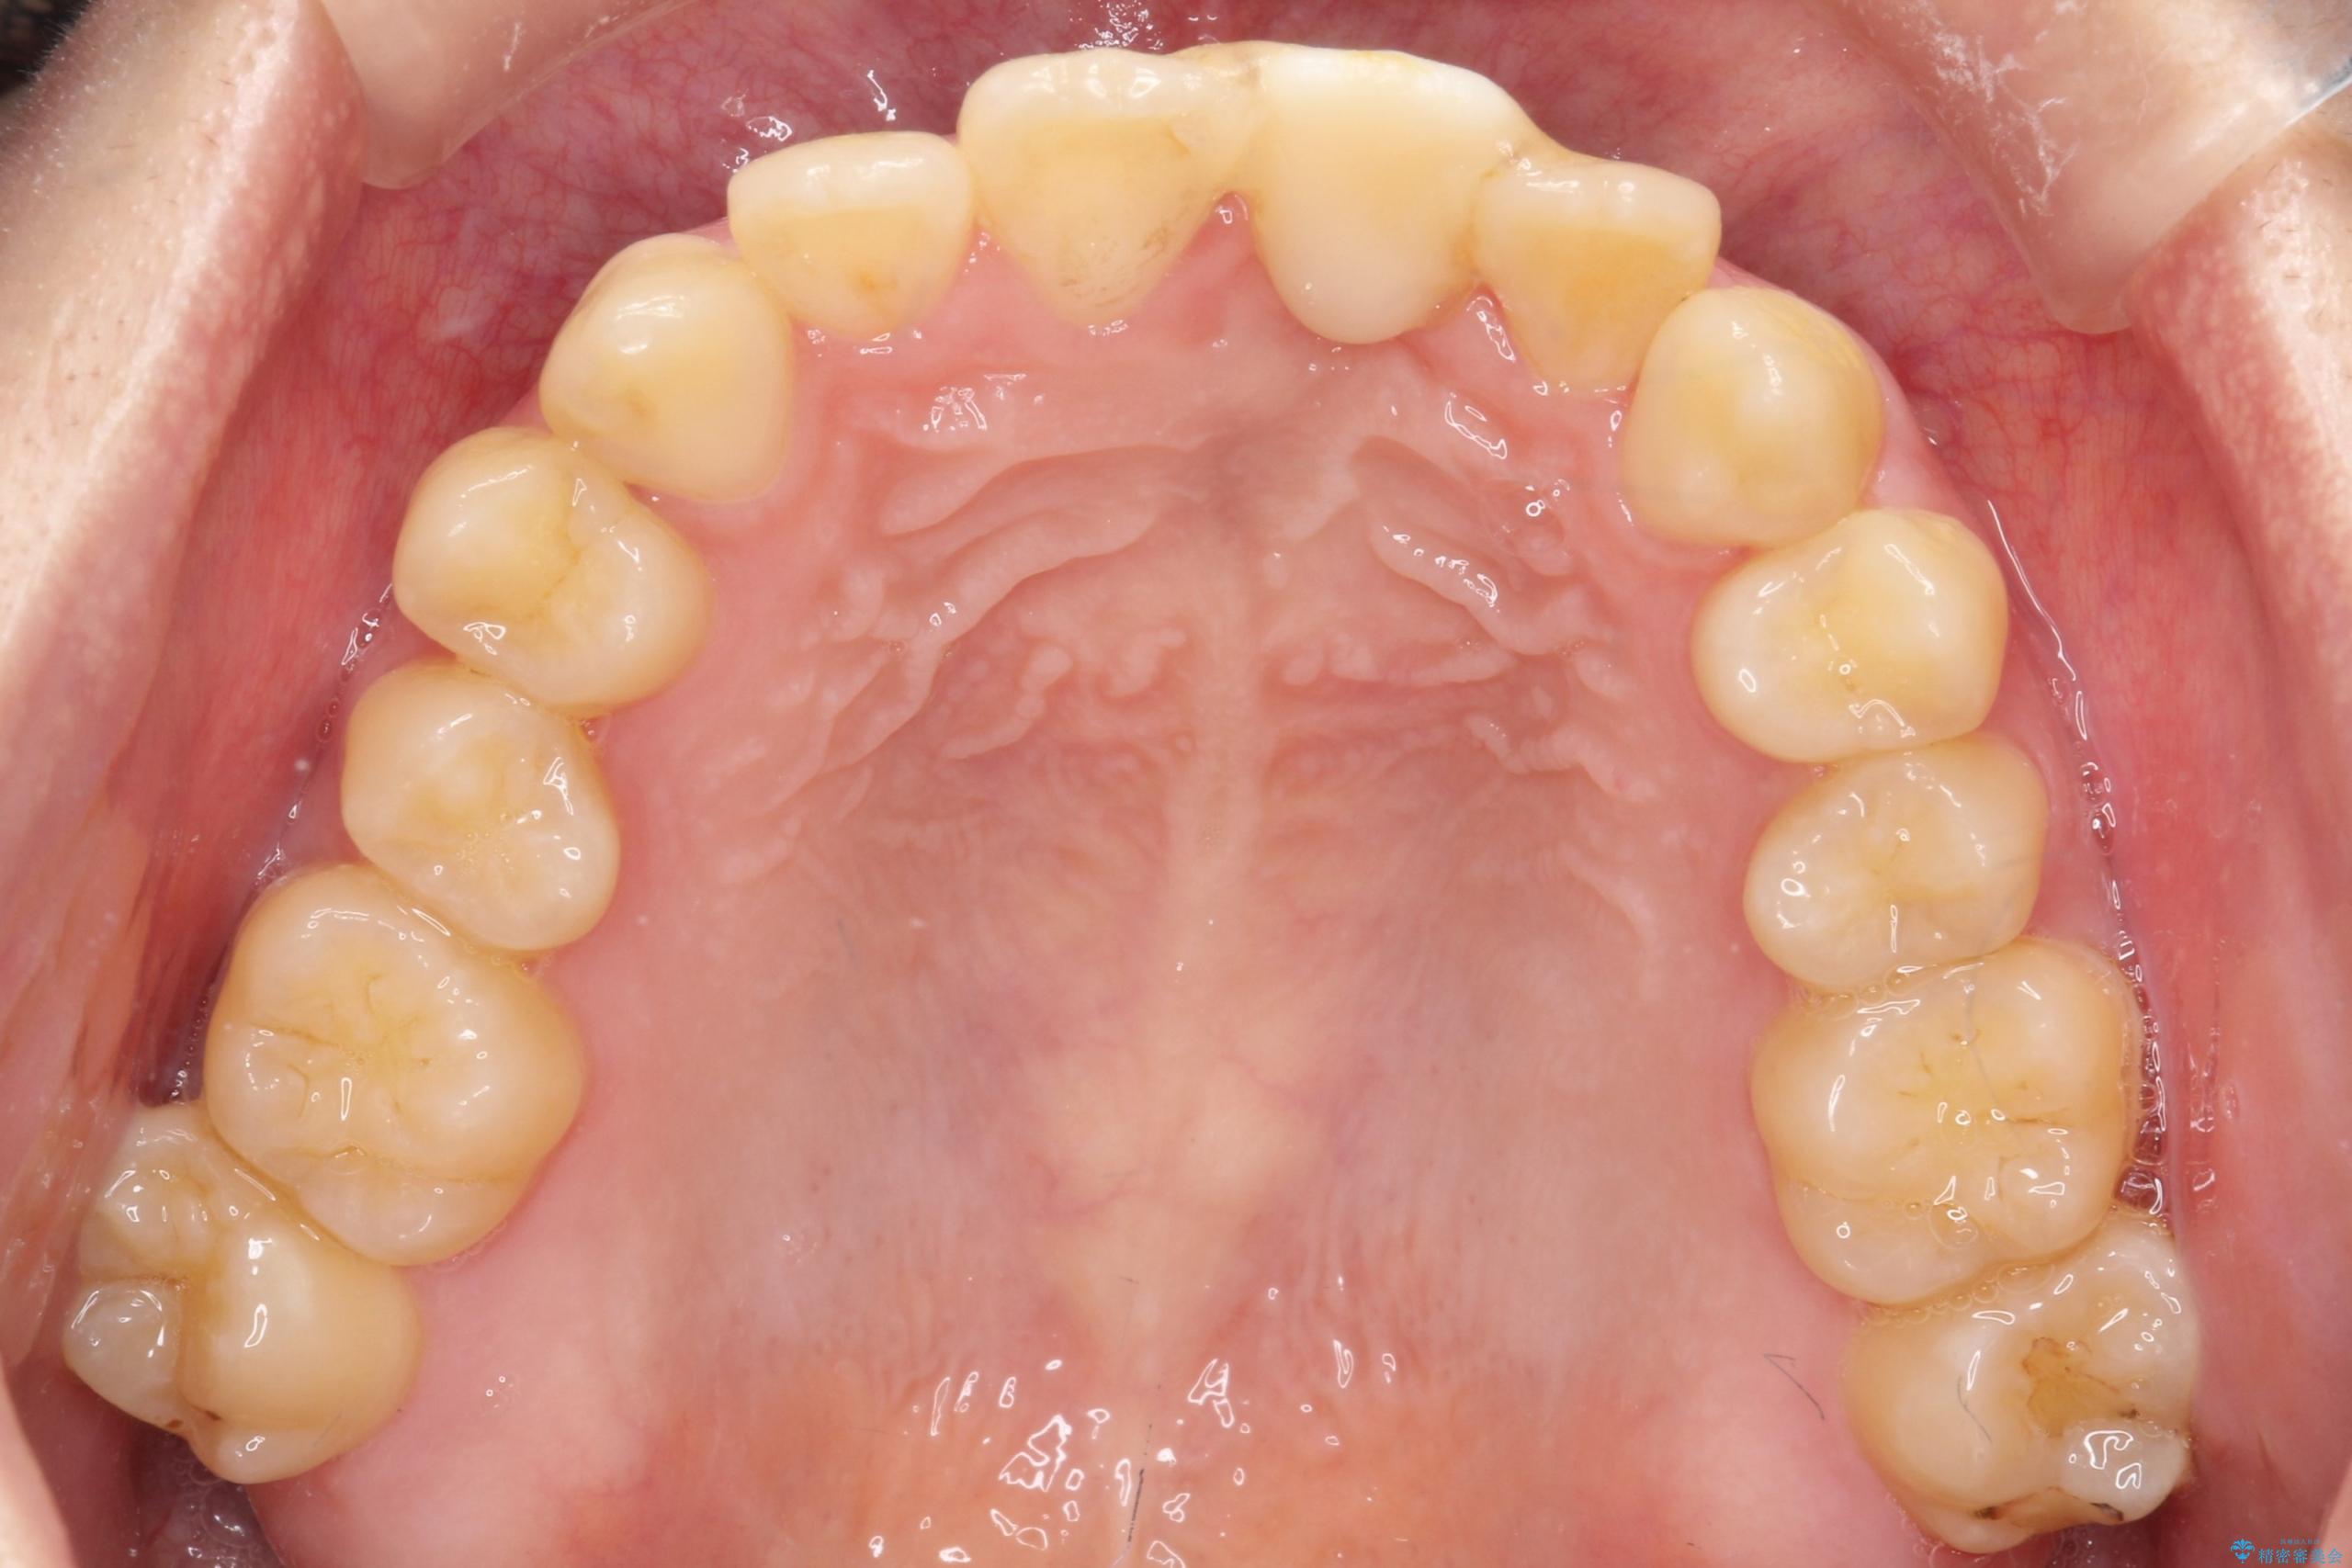

前歯の開咬とシザーズバイトを改善|インビザライン矯正

- 治療計画

前歯が噛まないため咀嚼が困難で、シザーズバイトにより噛み合わせに不調を感じていました。インビザラインを用いて、透明なマウスピースによる目立ちにくい矯正治療を実施。奥歯のシザーズバイトを改善した後、前歯の歯列を緻密に調整し、噛み合わせを整えました。定期的なマウスピース交換を通じて徐々に歯列が改善され、治療終了後には前歯が正常に咬合するようになり、噛み合わせの機能性と審美性が共に向上しました。